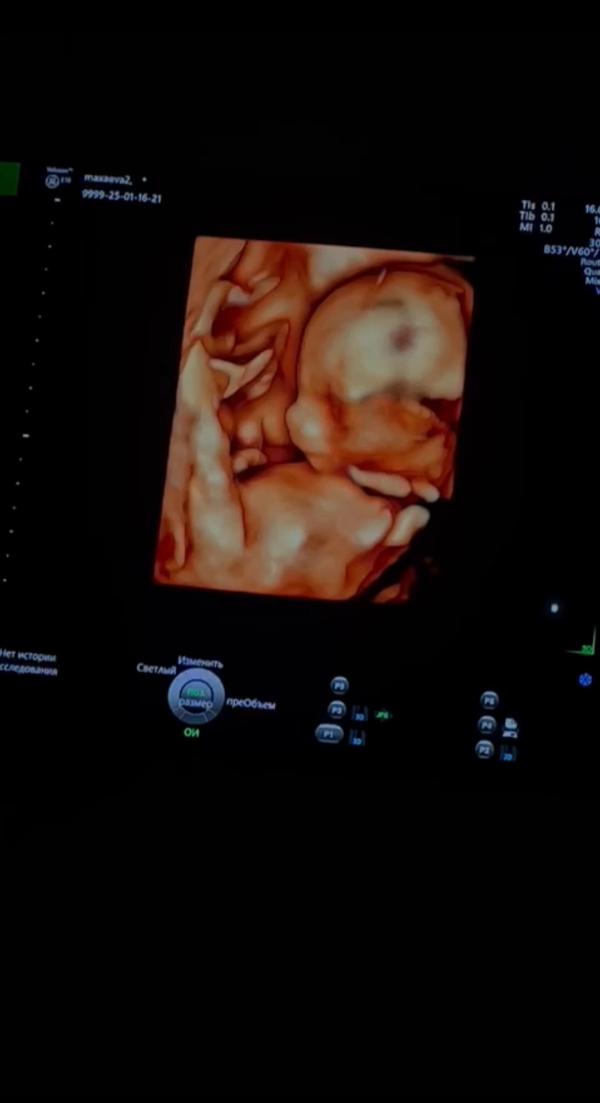

А как все начиналось то🥹💔